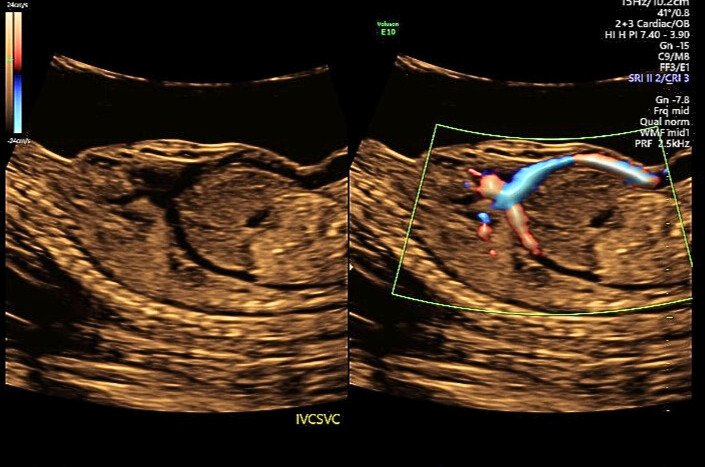

Absent Ductus Venosus

An ultrasound for Advanced Maternal Age revealed unexpected vascular abnormalities, raising concerns about potential complications. Further evaluation uncovered additional anomalies, prompting close monitoring and further testing.